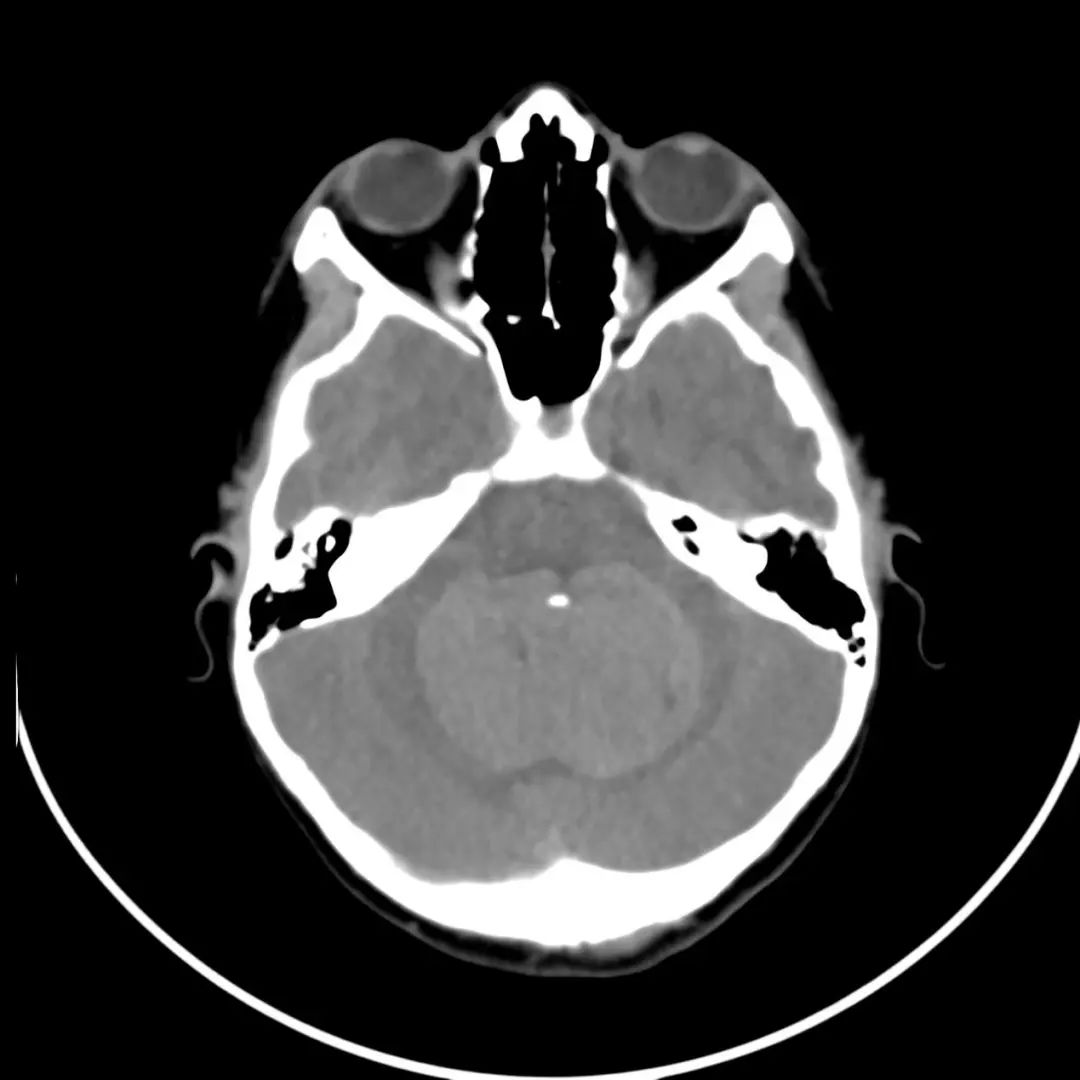

CT表现

- 病灶形态:圆形/卵圆形,边界清楚。

- 密度:多数略高,可见轻度瘤周水肿。

- 效应:儿童引起占位效应,可合并阻塞性脑积水。

- 增强后:均匀强化,囊变、坏死则不均匀强化。

中线小脑肿块,充满第四脑室并压迫脑干和小脑。与周围正常小脑相比,肿瘤在T1 WI上呈低信号,在T2 WI上呈轻度高信号,不均匀强化,呈囊/坏死成分,弥散受限。病理髓母细胞瘤。